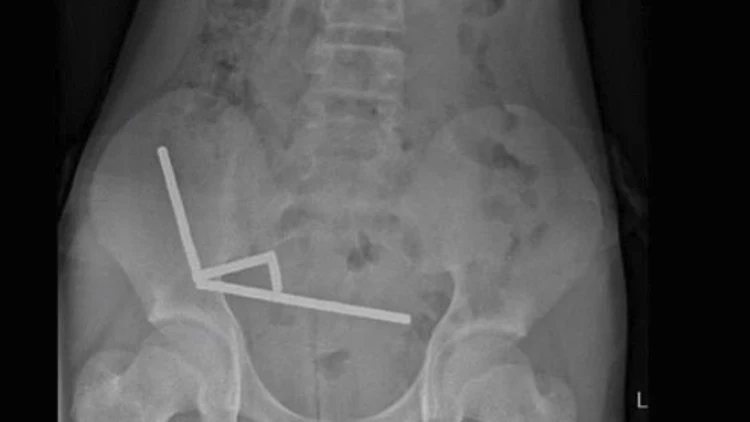

צילום הרנטגן חשף תמונה מדאיגה – המגנטים התקבצו והתחברו יחדיו בחלקים שונים של המעי. הניתוח כלל הסרה של הרקמות המתות וחילוץ של כל המגנטים. הנער שוחרר הביתה לאחר 8 ימים של אשפוז.